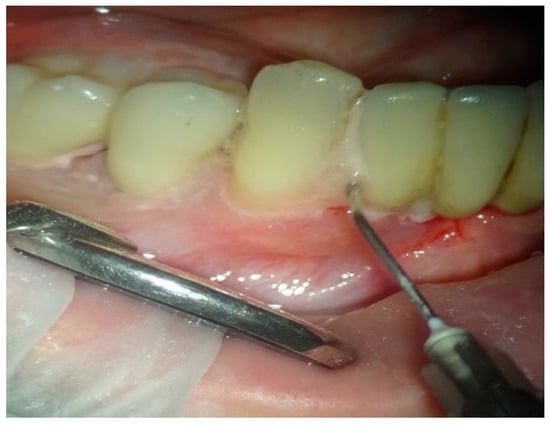

In group B, treated with the OHLLT protocol, a microbiological sampling of the periodontal pockets was made first. Then a supra and subgingival scaling with high-frequency ultrasound was made with a solution of Betadine diluted at 10% (Figure 1). An airflow session with erythritol was performed (Figure 2), and then diode laser treatment with a Sioxyl® solution was performed, irrigating the periodontal pockets with the Sioxyl® solution (Figure 3), leaving the solution for at least 2 min and irradiating with a Wiser diode laser with a peak power of 2.5 W, T-On of 20 microns, T-Off of 80 microns, average power of 0.5 W, duty cycle of 100 microns and frequency of 10 KHz (Figure 4).

Figure 3.

Irrigation with a Sioxyl solution.